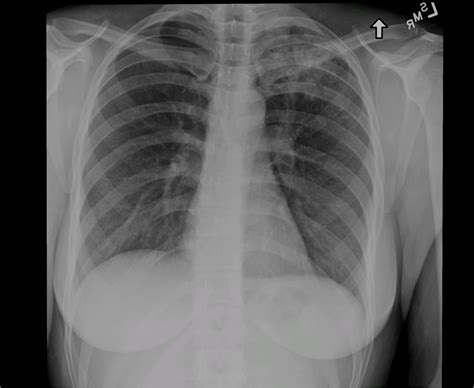

Interpreting Tb X Ray Results

Interpreting Tb X Ray results requires expertise and experience. Radiologists look for specific signs that may indicate TB:

• Cavities: These are hollow spaces in the lungs that can form as the body tries to contain the infection.

• Nodules: Small, round opacities that can be indicative of TB infection.

• Infiltrates: Areas of increased density in the lung tissue, often seen in active TB.

• Pleural Effusion: Fluid accumulation in the pleural space, which can be a complication of TB.

It’s important to note that while Tb X Ray can provide valuable information, it is not always conclusive. Additional tests, such as sputum tests or CT scans, may be required for a definitive diagnosis.